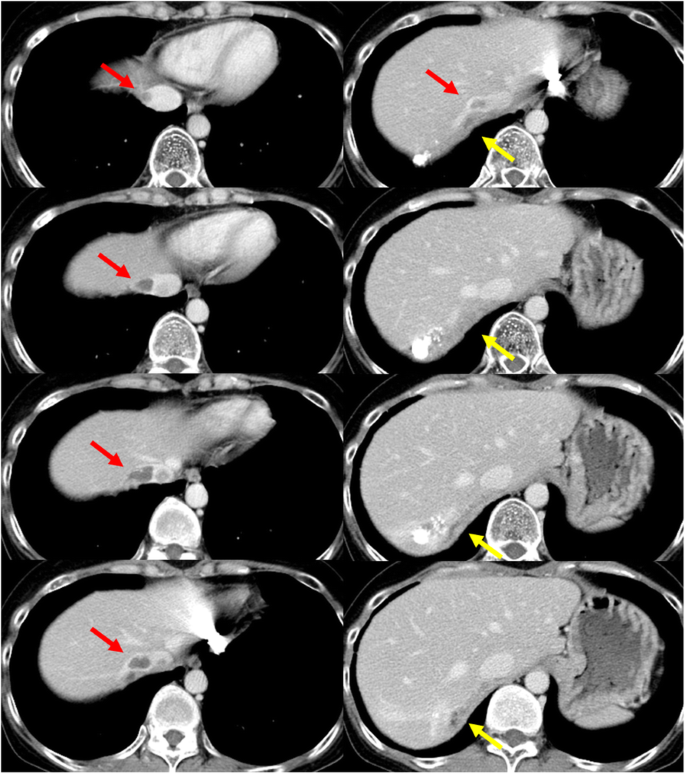

The patient was a 75-year-old woman with chronic hepatitis C viral infection. Repeated TACE, percutaneous ethanol injection therapy, and radiofrequency ablation had been performed for multiple HCCs of both lobes during 8 years before our surgery. After these treatments, a low-density area was recognized under the diaphragm with a tumor thrombus (Fig. 3).

Dynamic-enhanced computed tomography imaging of case 3. Tumor thrombus was detected in the right hepatic vein, inferior vena cava (IVC), and right atrium (RA; red arrow), as well as in the right phrenic vein (yellow circle). The left column shows the axial view, and the right column shows the coronal view